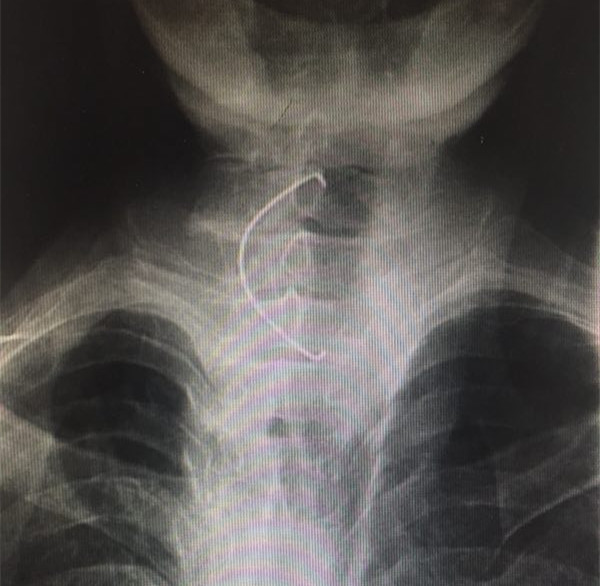

该患者系82岁男性,去年6月份因“误咽假牙”之主诉急诊入院。食道钡透显示“食道上段异物”,在全麻下顺利取出假牙,交给患者家属。该假牙为上颌部全假牙,长约7公分,患者平安出院。近日该患者再次“误咽假牙8小时”急诊入院,经询问才知道,患者去年误咽的假牙回家后仍继续使用,导致假牙再次误咽,经食道钡透证实为“食道上段异物”,全麻下顺利取出,告知患者及其家属,此假牙不合适,不能使用,需重新配假牙。该患者两次手术住院费远远超过配假牙费用,且高龄老人全麻手术有很大风险。